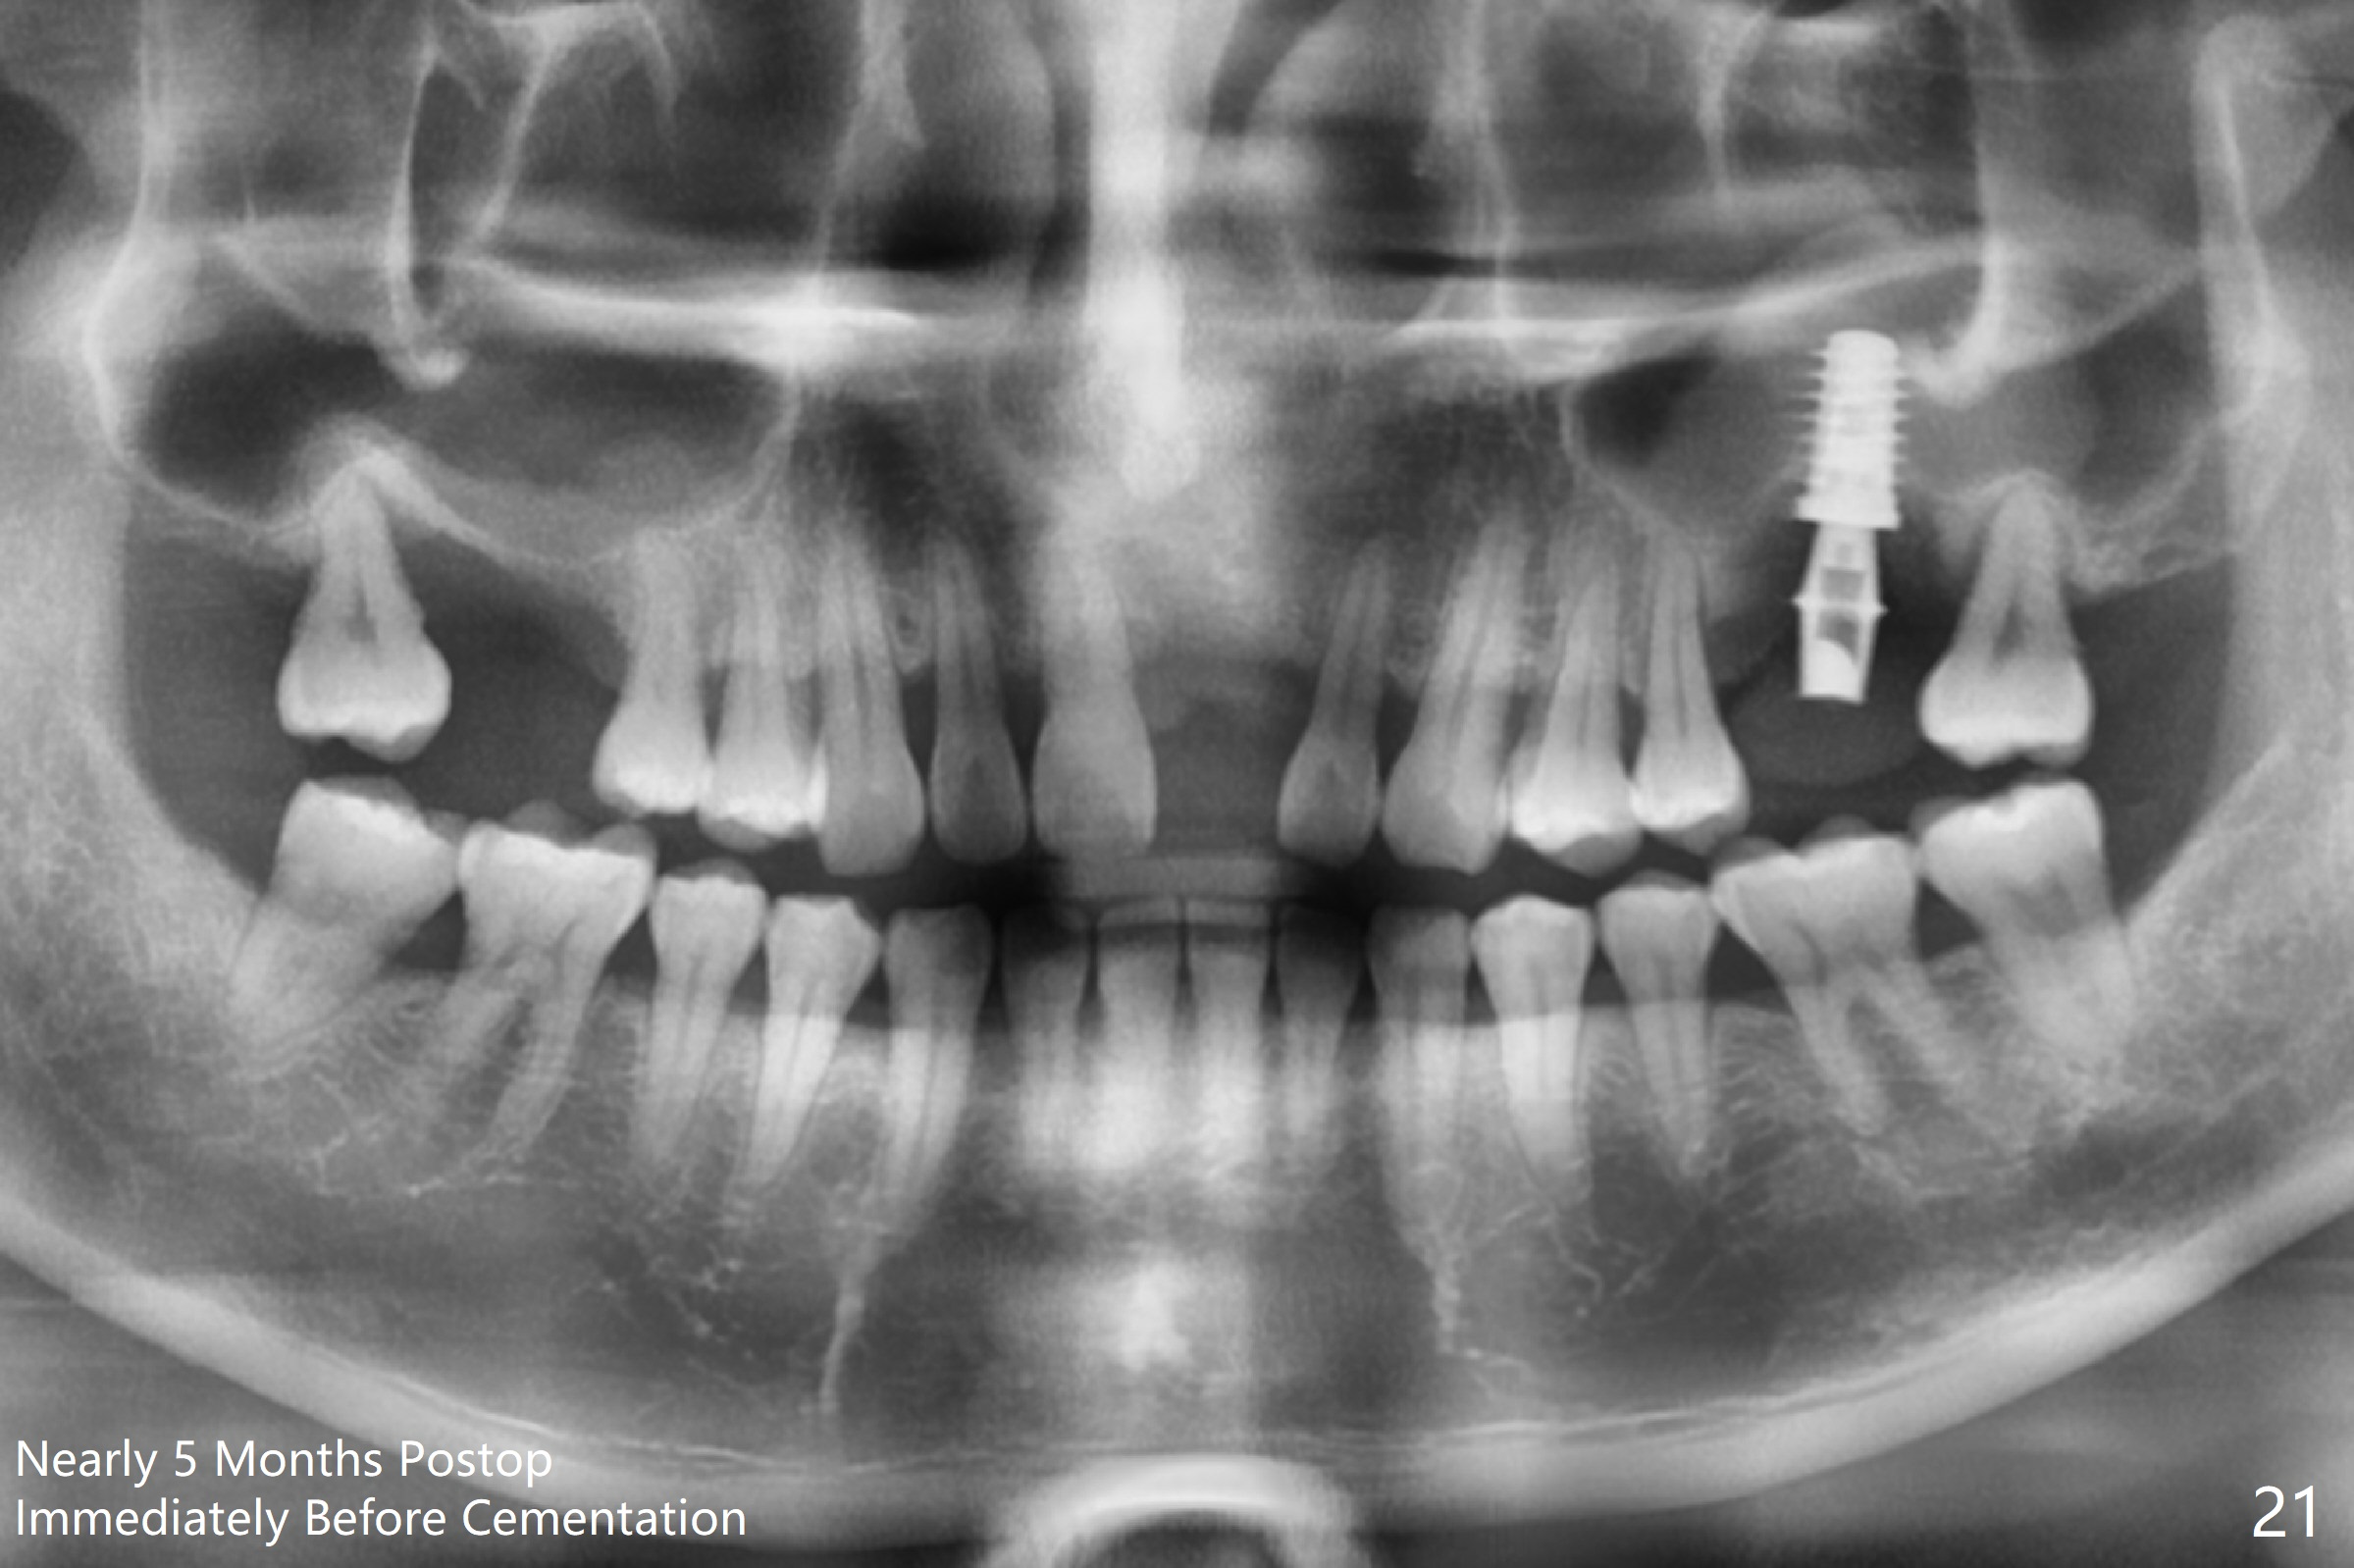

There is a mushroom around the implant nearly 5 months postop/immediately before cementation (Fig.21).  The bone density around the implant is low (Fig.22-24' *).